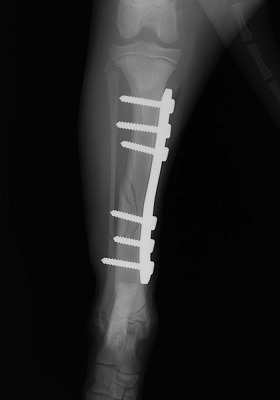

家の中で遊んでいると「キャイーン」という悲鳴と共に片方の足を地面に付く事が出来なくなり来院されました。レントゲンを撮り調べてみると骨折していることが判明。

Img5977-1.jpg